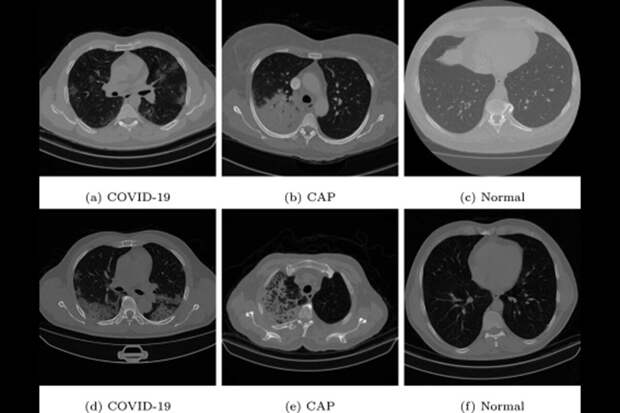

Для обучения нейросети ученые воспользовались набором срезов компьютерной томографии COVID-19, полученных в разных странах. Он содержит более 7500 снимков легких, пораженных ассоциированной с коронавирусом пневмонией, более 2500 снимков легких с внебольничной пневмонией и почти 7000 снимков здоровых легких.Результаты четырехкратной перекрестной проверки новой нейросети доказали ее точность и эффективность. По словам исследователь, модель имеет большой потенциал для точной и быстрой диагностики COVID-19 с использованием изображений компьютерной томографии.